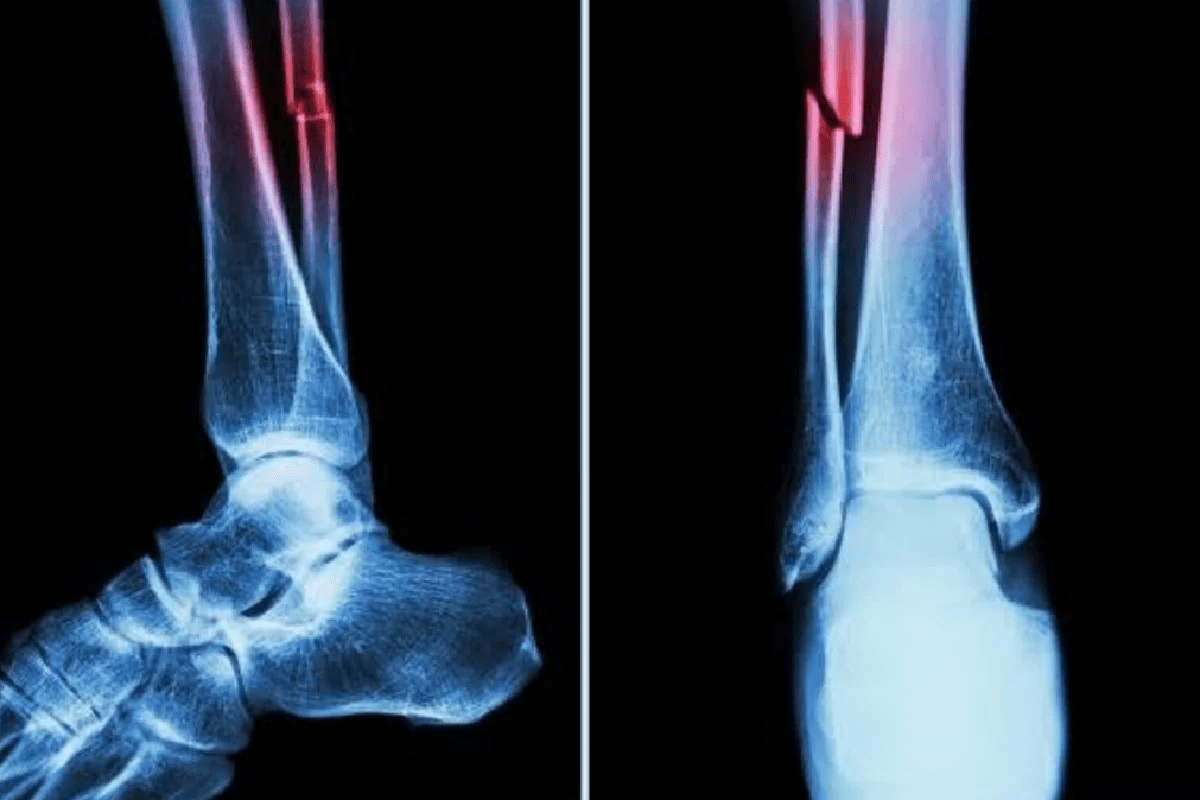

Understanding Tibia Bone Fractures

The tibia, or shinbone, is the most common long bone in the body to be broken. Tibia bone fractures often result from high-energy trauma like car accidents or heavy falls.

- Pilon bone fracture: A specific and severe type of tibia break involving the weight-bearing surface of the ankle.

- These injuries often involve significant damage to the surrounding soft tissues and skin.

- Recovery requires expert alignment to ensure the ankle joint remains functional.

At Liv Hospital, we treat tibia bone fractures with a focus on preserving the blood supply to the bone, which is essential for the immune system to deliver healing cells to the injury site.